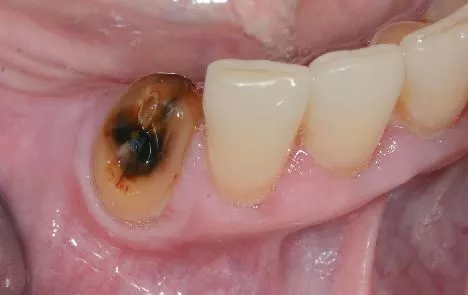

Eine weibliche, 72-jährige Patientin stellte sich acht Wochen nach Extraktion des Zahnes 44 alio loco in unserer Sprechstunde vor. Allgemeinanamnestisch besteht eine dauerhafte antiresorptive Therapie mit Bisphosphonaten für mehr als zehn Jahre zur Behandlung einer Osteoporose. Der operative Eingriff erfolgte ohne antibiotische Abschirmung. Klinisch zeigte sich in regio 44 vestibulär freiliegender Knochen.

Beschwerden gab die Patientin keine an. Nach ausführlicher Aufklärung der Patientin erfolgte eine chirurgische Wundrevision mit Abtragung des nekrotischen Knochens und spannungsfreier plastischer Deckung. Eine antibiotische Abschirmung erfolgte vom Zeitpunkt der Vorstellung bis zehn Tage postoperativ. Bei Nahtentfernung zeigten sich reizfreie Wundverhältnisse (Abb. 2).